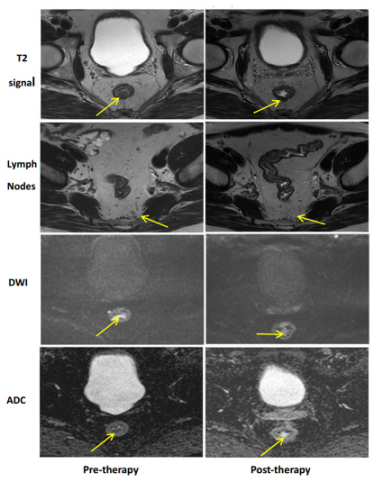

| MRI-T2W | Only a dark T2 signal; no intermediate signal AND No visible lymph nodes | Mostly dark T2 signal, some intermediate signal AND/OR Partial regression of lymph nodes | More intermediate than a dark T2 signal, no T2 scar AND/OR No regression of lymph nodes |

| MRI-DWI | No visible tumor on the B800–B1000 signal AND/OR Lack of or low signal on the ADC map A uniform linear signal in the wall above the tumor is acceptable | Significant regression of the signal on B800–B1000 AND/OR Minimal or low residual signal on the ADC map | Insignificant regression of signal on B800–B1000 AND/OR Obvious low signal on the ADC map |

| Complete Response | Near-Complete Response | Incomplete Response |

![]() | ![]() | ![]() |